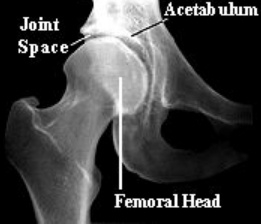

首先,让我们来认识髋关节的基础解剖。髋关节基本上是一个球状关节,骨盆像是一个冰淇淋勺一样将髋关节包在里面。我们的股骨最上端,称为「股骨头」,是一个球状的关节。举凡在身上的球状关节,它们活动度都应该要很大,它生来就该是灵活的!我们的髋关节跟肩关节就是球状关节。

在股骨头上,有许多的肌肉、关节囊,以及结缔组织。这些构造都深深地影响着深蹲。但我们今天单纯讨论骨头的部分。(下图为髋关节的X光检查)